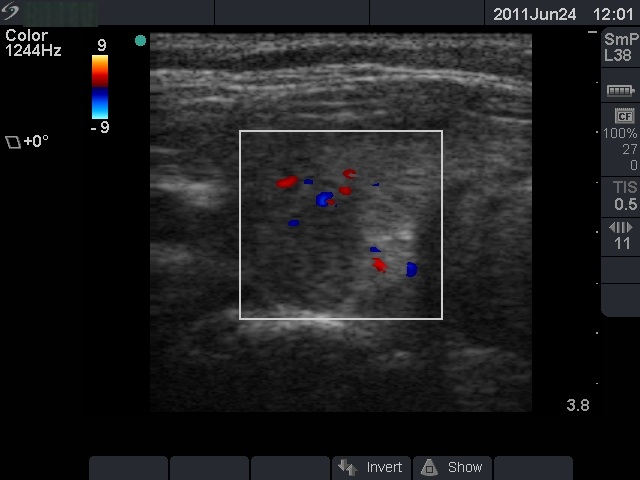

Subacute granulomatous de Quervain's thyroiditis - Case 24. (ultrasonographic picture 6)

Left lobe, longitudinal scan, color Doppler mode. The vascularization is not specific in this view.